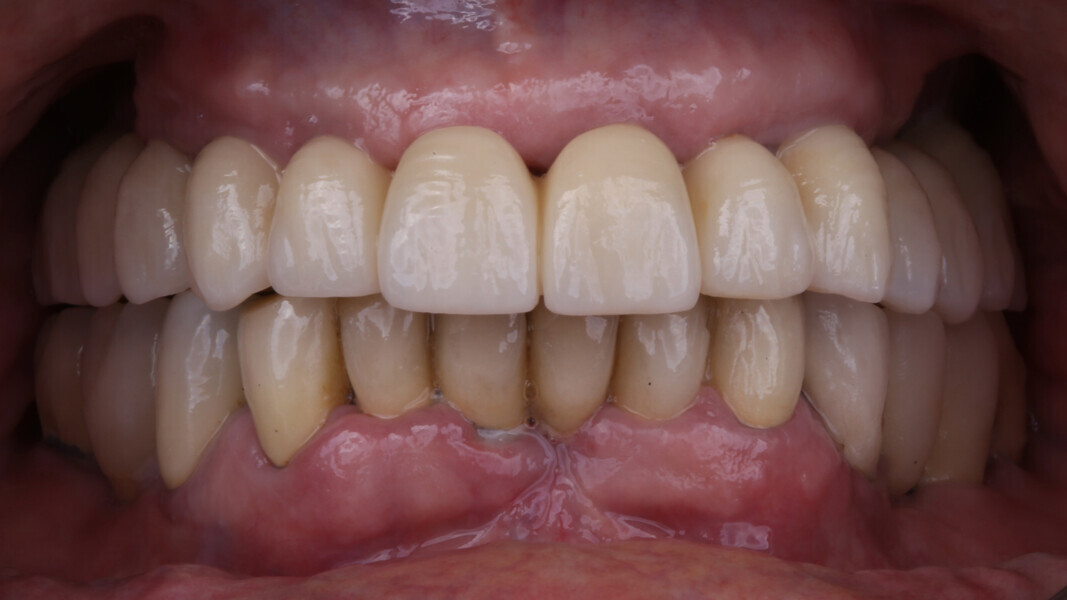

Fig. 1: Initial situation, frontal view. (All images: Dr Marco Tallarico et al.)

An 85-year-old partially edentulous patient was referred to our clinic for full-arch rehabilitation of the maxilla. The patient was in good general health and a non-smoker. His primary complaints included difficulty in chewing, maxillary pain and occasional halitosis. Clinical and radiographic evaluation revealed a short-span fixed metal–ceramic prosthesis supported by seven anterior maxillary teeth. The prosthesis had debonded, and four of the abutment teeth were structurally compromised. The remaining three showed varying degrees of caries and periodontal problems. A diagnosis of failing dentition was established (Figs. 1 & 2).

At the final appointment, the definitive hybrid screw-retained prosthesis was delivered. The definitive prosthesis consisted of a CAD/CAM titanium framework screwed on to all of the implants and three monolithic zirconia prosthetic segments bonded on top (Figs. 18a–c). The occlusion was evaluated, and the patient was enrolled in a four-month maintenance programme. At the last follow-up (one year after implant placement), all of the implants were successful and the patient was fully satisfied with the new prosthesis (Figs. 19–22).